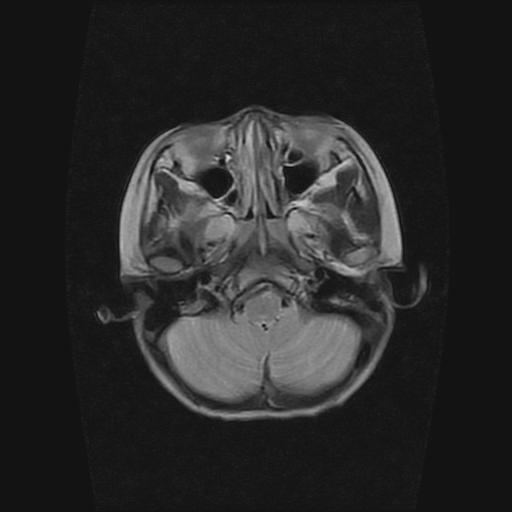

6岁小儿,左侧视神经瘤术后。现左侧视力减退。